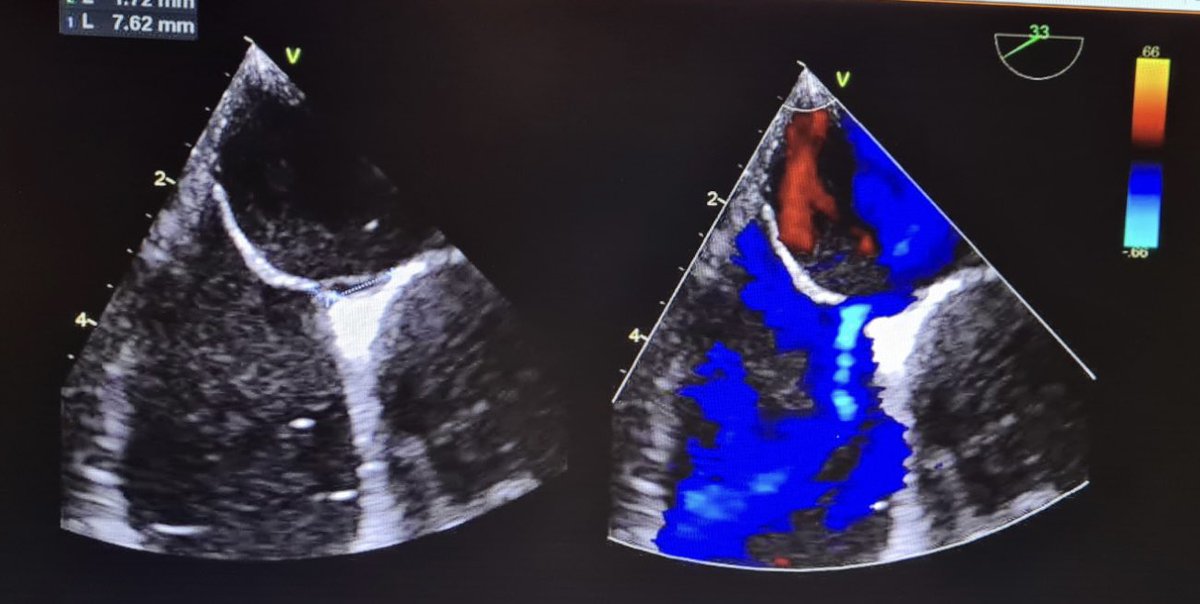

Os médicos acharam uma característica no coração do paciente chamada Forame Oval Patente que *às vezes* (não em todos que têm) pode ter relação com formação de coágulos no coração que podem migrar para o cérebro, causando um AVC.

Mas em cerca de 1/4 das pessoas normais, pode acontecer deste orifício não fechar, deixando uma pequena comunicação entre os átrios. É o que se chama de Forame Oval Patente (FOP).

Como o paciente não tinha nenhum problema que pudesse gerar distúrbios de coagulação, suspeitaram que o FOP poderia ter favorecido a ocorrência do AVC.

Ele foi operado e fecharam a comunicação entre os átrios colocando com uma prótese amplatzer (foto). Agora, o paciente, que é cardiologista, passa bem.

Outros personagens do fio: Tomografia mostra avc no cérebro.Ecocardiograma